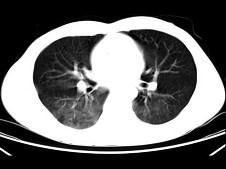

男,35岁,被车撞伤后1小时,结合影像图像选择其最可能的诊断为 ( )A、肺挫伤B、支气管扩张C、肺结核D、间质性肺炎E、肺炎

问题 男,35岁,被车撞伤后1小时,结合影像图像选择其最可能的诊断为 ( )

选项 A、肺挫伤 B、支气管扩张 C、肺结核 D、间质性肺炎 E、肺炎

答案 A